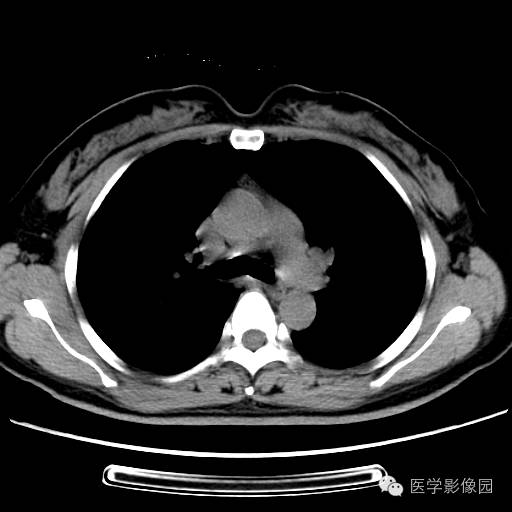

肺叶实变性支气管肺泡癌1例CT影像表现